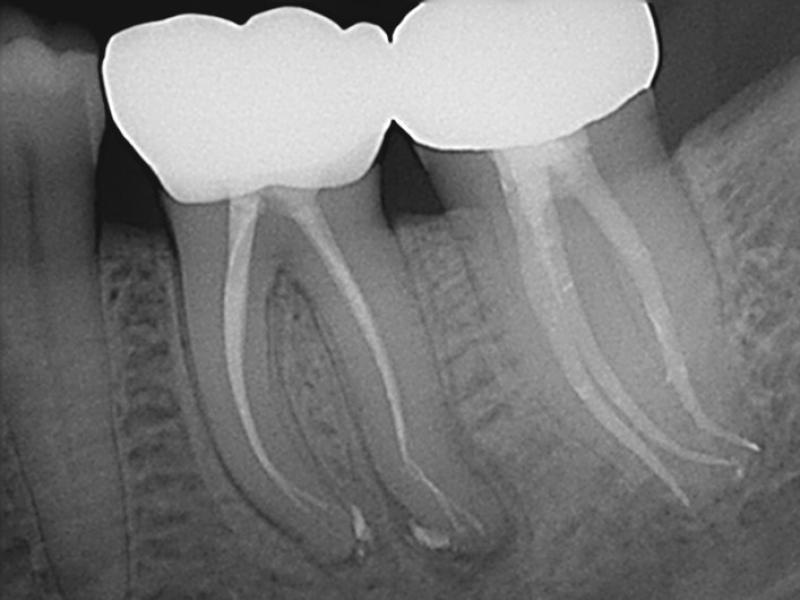

Recall